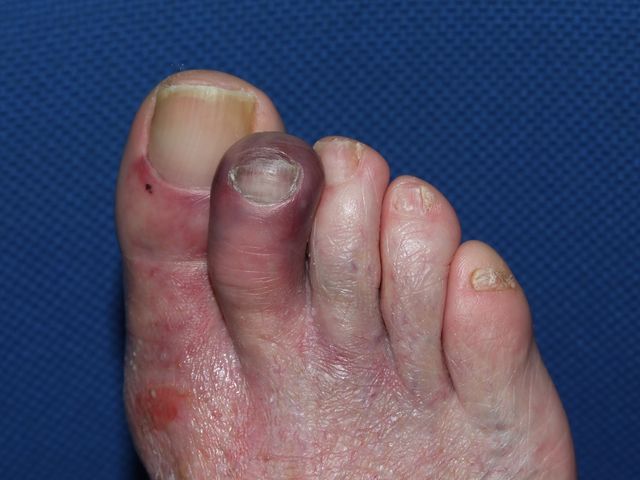

Podagra gotosa.